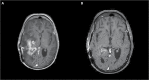

Figures